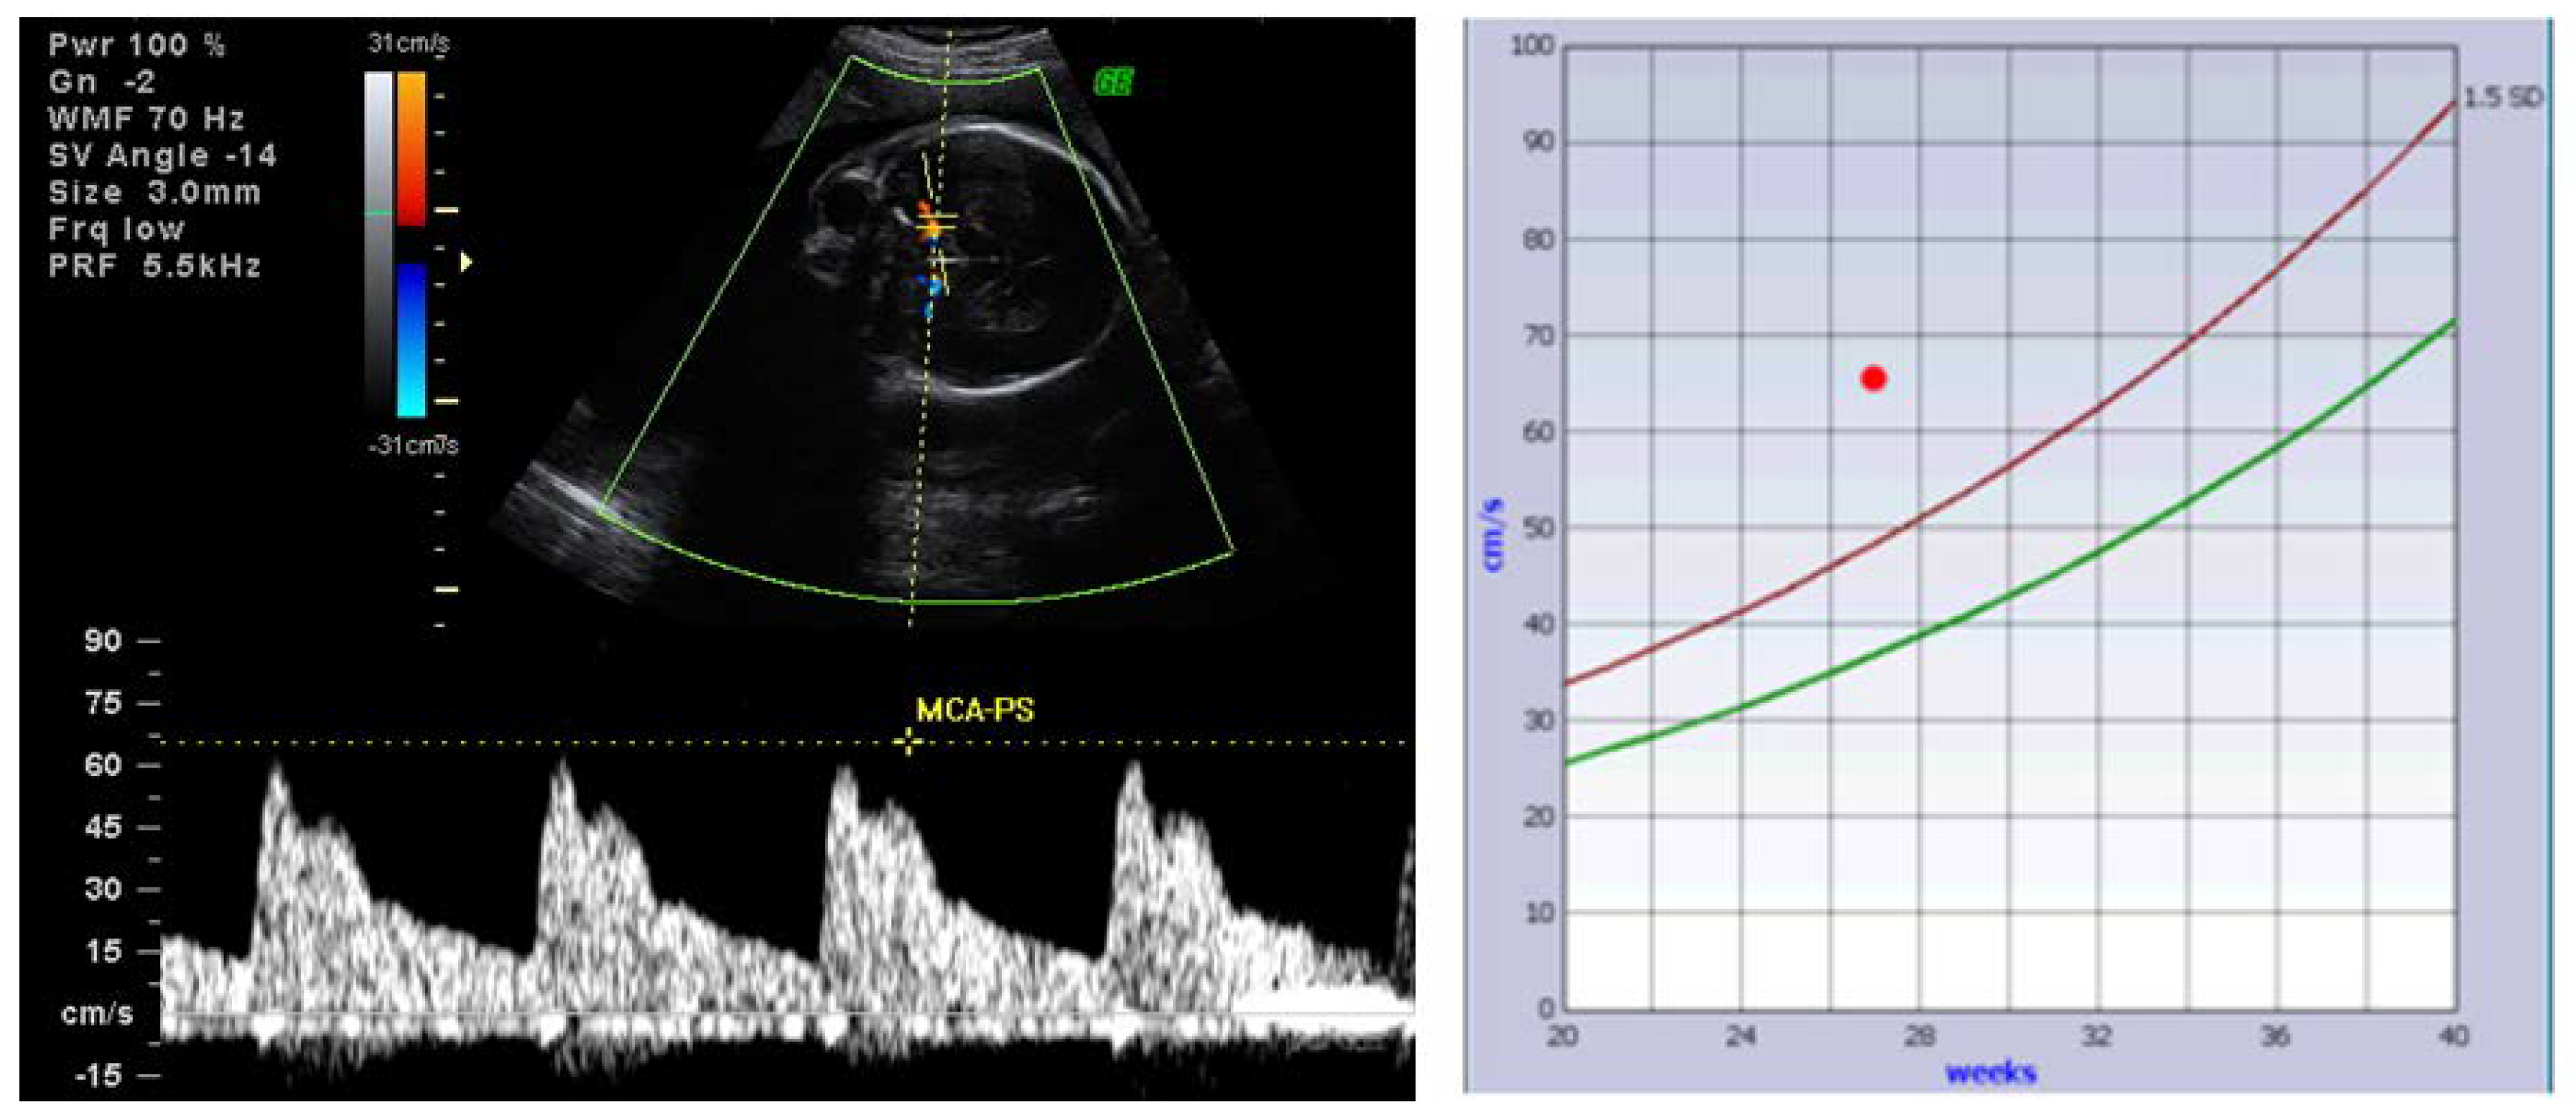

4.1. Alloimmune Hemolytic Disease of the Fetus and Newborn (HDFN)—Anti-Red Cell Antibodies